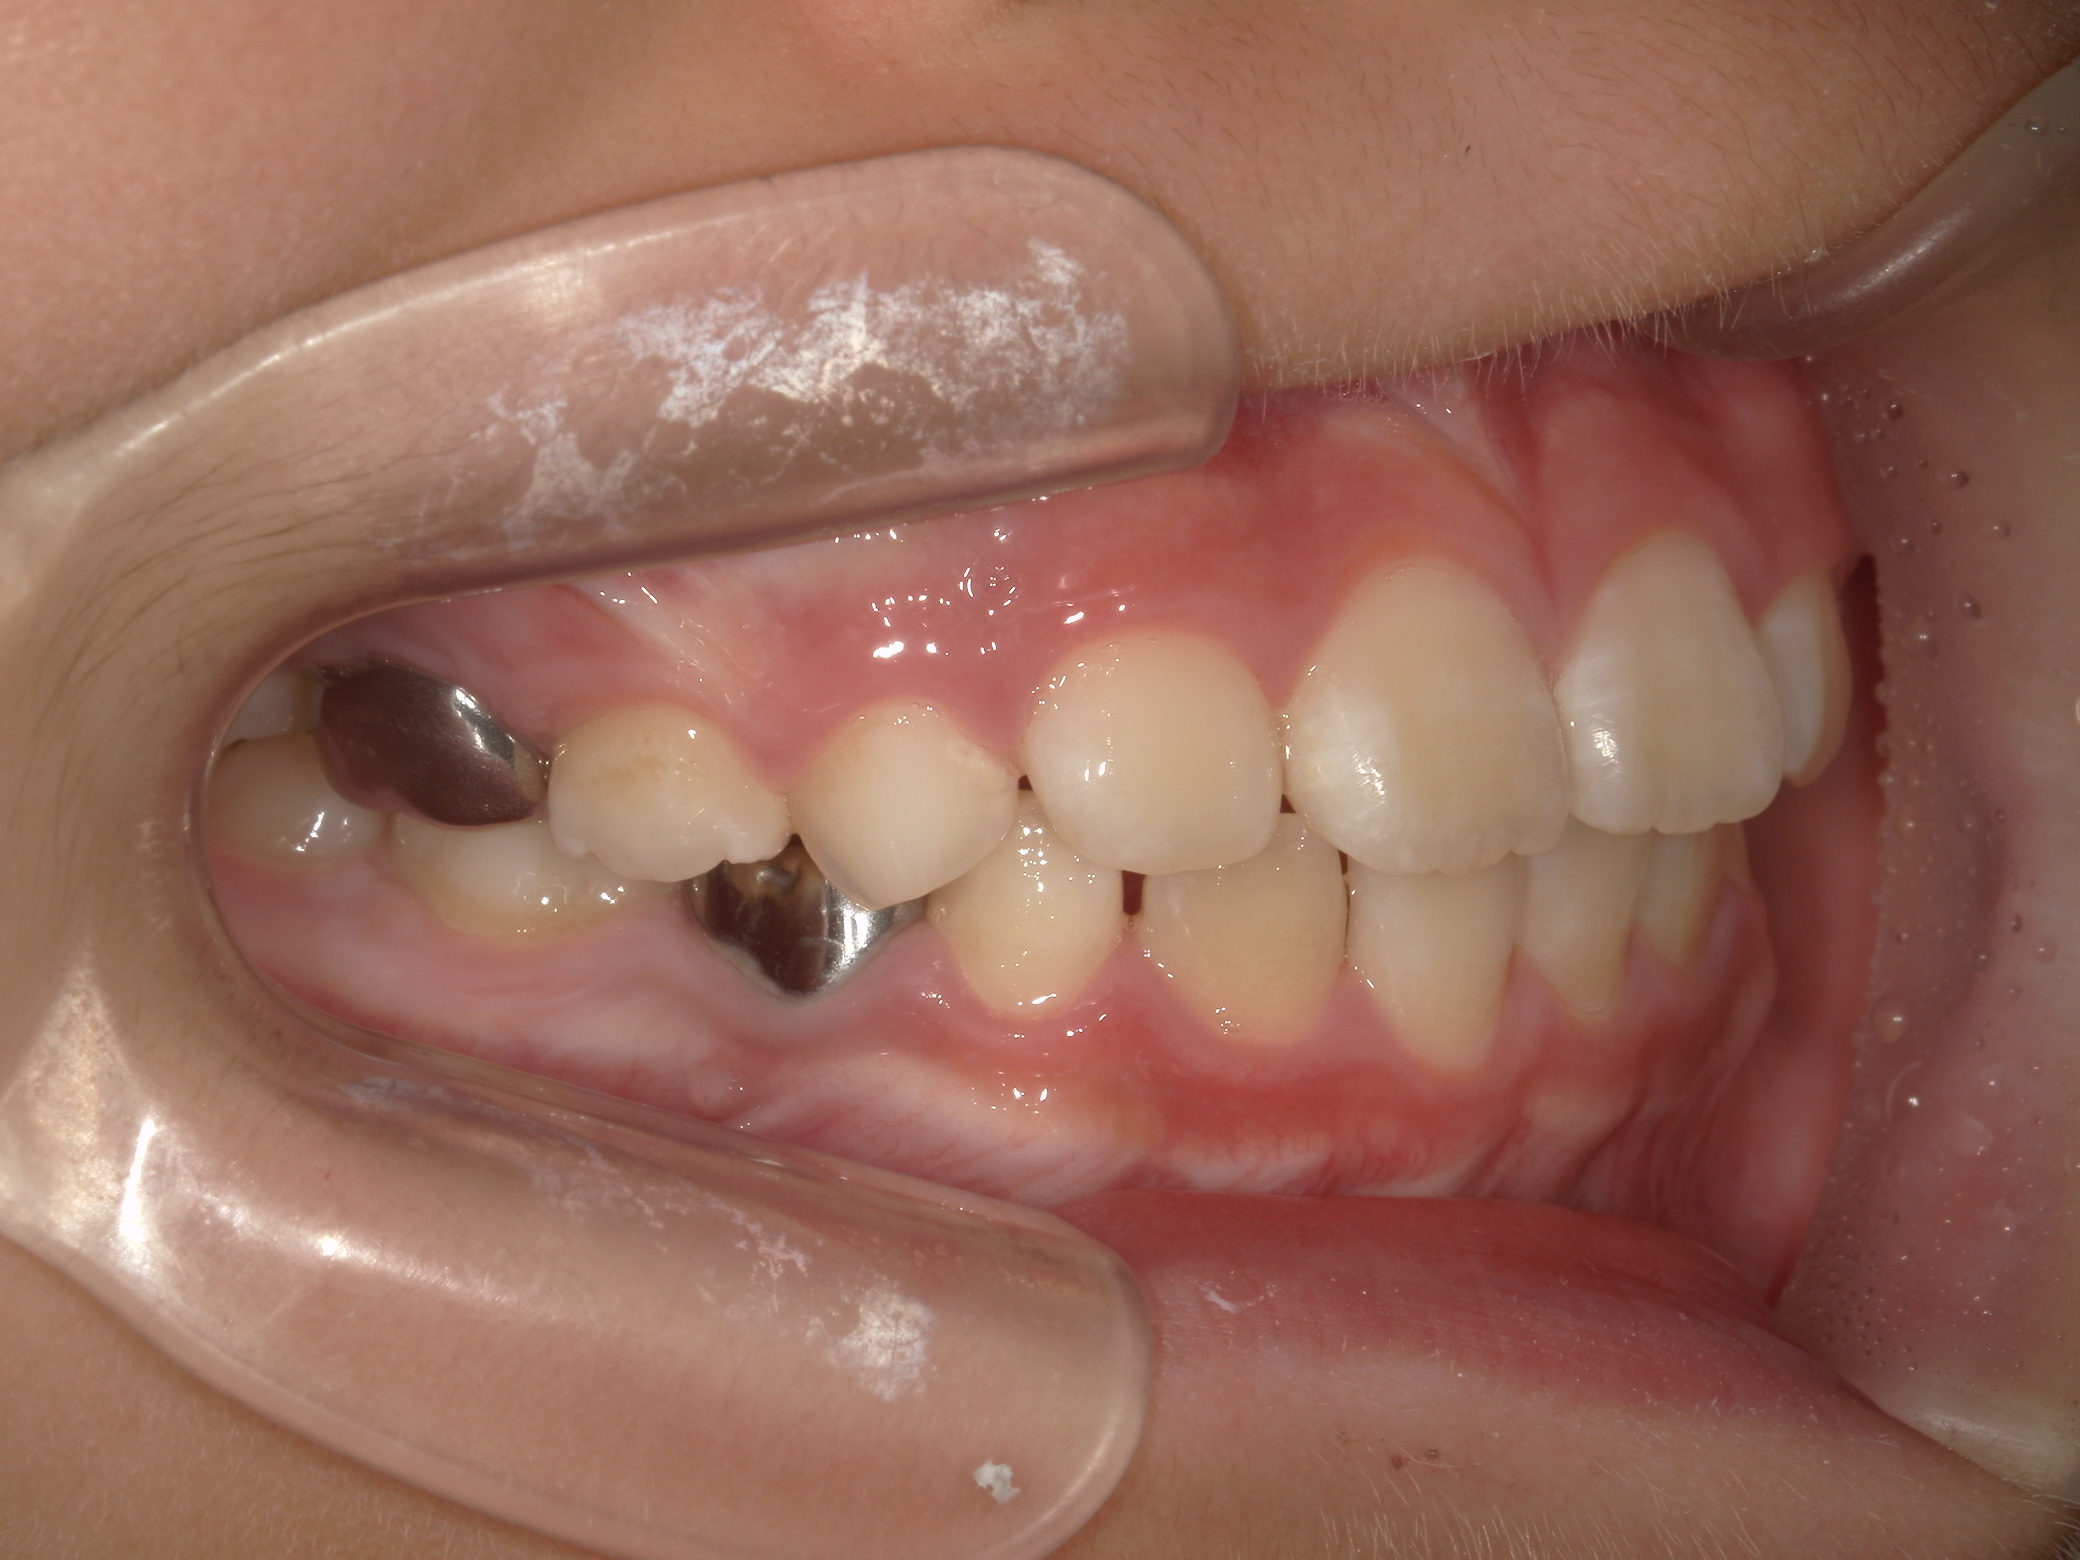

【小学生】マイオブレース矯正 反対咬合(受け口)を改善

小学生で開始

マイオブレース

受け口

非抜歯

1期治療のみで改善

Before

After

治療期間

1.6年

治療開始

8歳

種類

マイオブレース矯正

使用装置

機能矯正装置

コメント

装置装着と 筋機能療法をきっちり取り組んでくれましたので

スムーズに治りました。

現在も安定して 後戻りしていません。